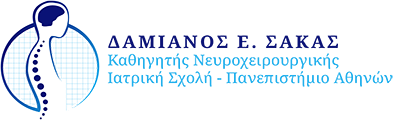

Εικόνα 1. Γλοίωμα στην κροταφοβρεγματική περιοχή του εγκεφάλου δεξιά, με έντονο οίδημα που το περιβάλλει και παρεκτοπίζει την μέση γραμμή του εγκεφάλου προς τα αριστερά. Ειναι εμφανής η ανομοιογένεια του όγκου, χαρακτηριστικό των γλοιοβλαστωμάτων.